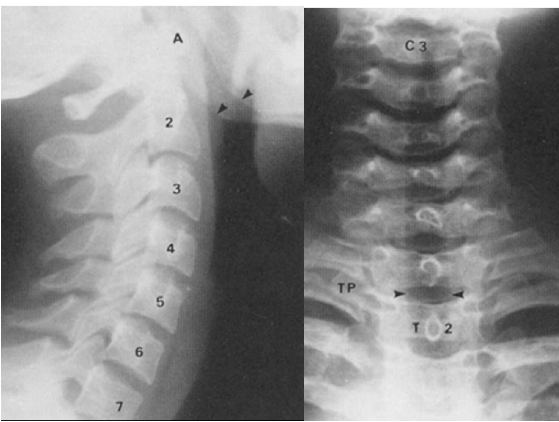

xray image of cspine